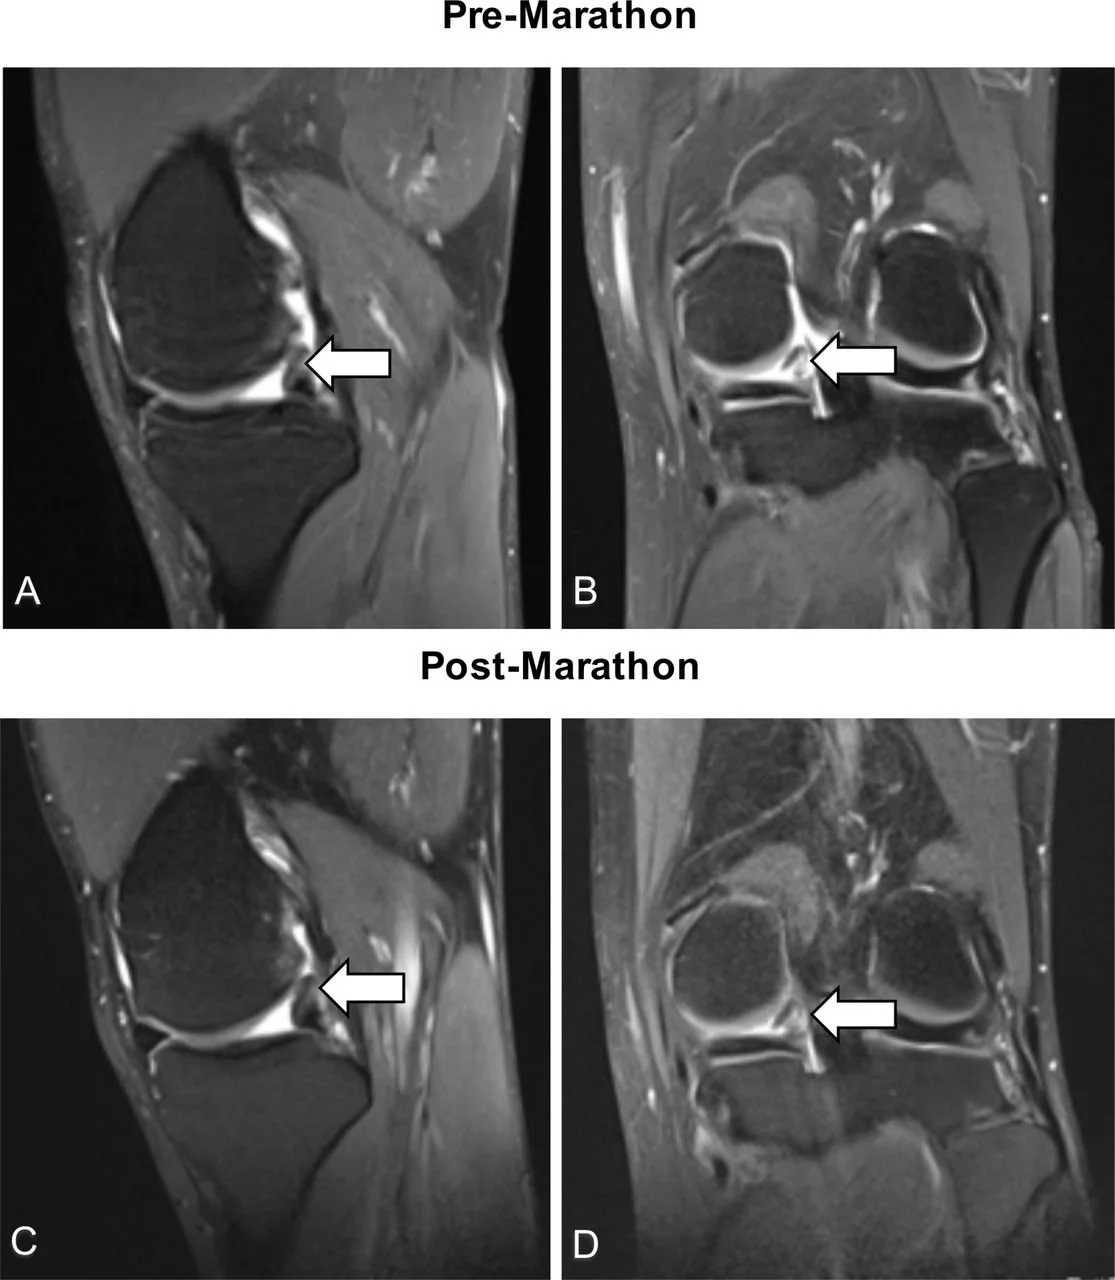

Few studies have investigated the effects of marathon running specifically on the internal knee structures. MRI provided us with the perfect tool to assess whether running a marathon changes the ‘normal’ structure of the knee. With this study we wanted to better understand the effect of marathon running on the knee joint by performing high resolution 3T MRI scans of both knees of first-time marathon runners before and after running a marathon.

The main weight-bearing compartments presenting subchondral bone marrow oedema before the marathon, in asymptomatic middle-aged adults, showed reversibility following the training for and completion of running a marathon.

The patellofemoral compartment was the region most injured by marathon running.